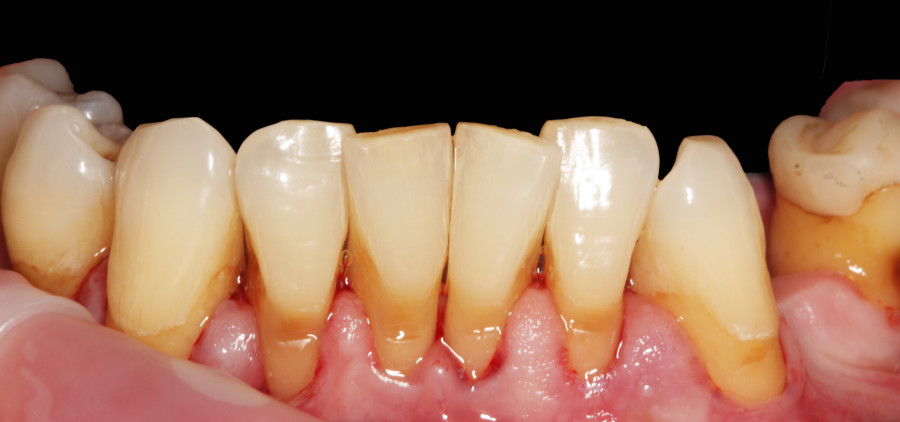

Pacjent lat 60, duże recesje dziąseł, niewyedukowany w zakresie prawidłowej higieny jamy ustnej. Został skierowany na higienizację profesjonalną przez lekarza prowadzącego. Na pierwszej wizycie siekacze dolne pacjenta wyglądały tak: zdjęcie 1, zdjęcie 4.

Widać wyraźnie, że kamień i gruba warstwa płytki bakteryjnej wywołał stan zapalny dziąseł – są przekrwione, i opuchnięte. Higienistka wykonała skaling naddziąsłowy skalerem EMS, wypiaskowała zęby piaskiem Air-Flow Plus oraz wypolerowała pasta polerską. Po zabiegu różnica wyglądzie zębów jest diametralna: zdjęcie 2, zdjęcie 5.